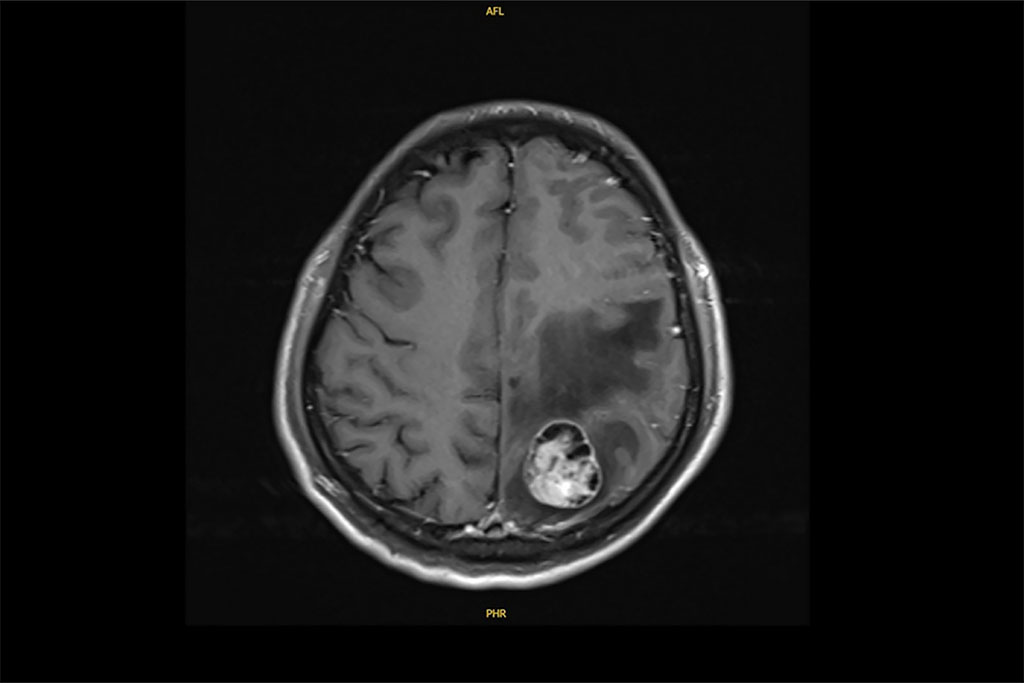

今年41歲的許先生,原從事文具業務,是家中主要經濟支柱;三年前(2022年)6月某日清晨,突然出現右側肢體無力與抽搐,倒地不起。家人驚慌之下緊急送至彰基急診。經電腦斷層及核磁共振檢查,醫師發現腦部有約3.1公分腫瘤,進一步追蹤又在右下肺發現4公分腫塊,確診為肺腺癌合併腦轉移。

許先生的腦部核磁共振檢查發現腫瘤達3.1公分,進一步確診為肺腺癌轉移。